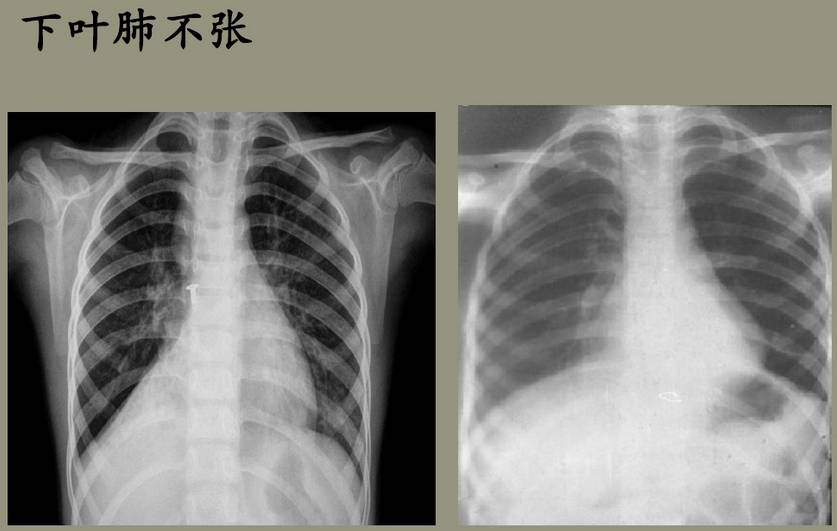

(4)下叶不张:下叶肺不张使其向后、向内收缩至脊柱旁沟区,肺门向下、向内移位。左下叶不张易被心影掩盖,肺门影向下移位,并往往与心影重叠,左膈顶上升,舌叶动脉阴影下移等,为提示有下叶不张的重要依据。下叶不张由于前缘向后旋转,在侧位片上可以不能见到,需斜位片显示。